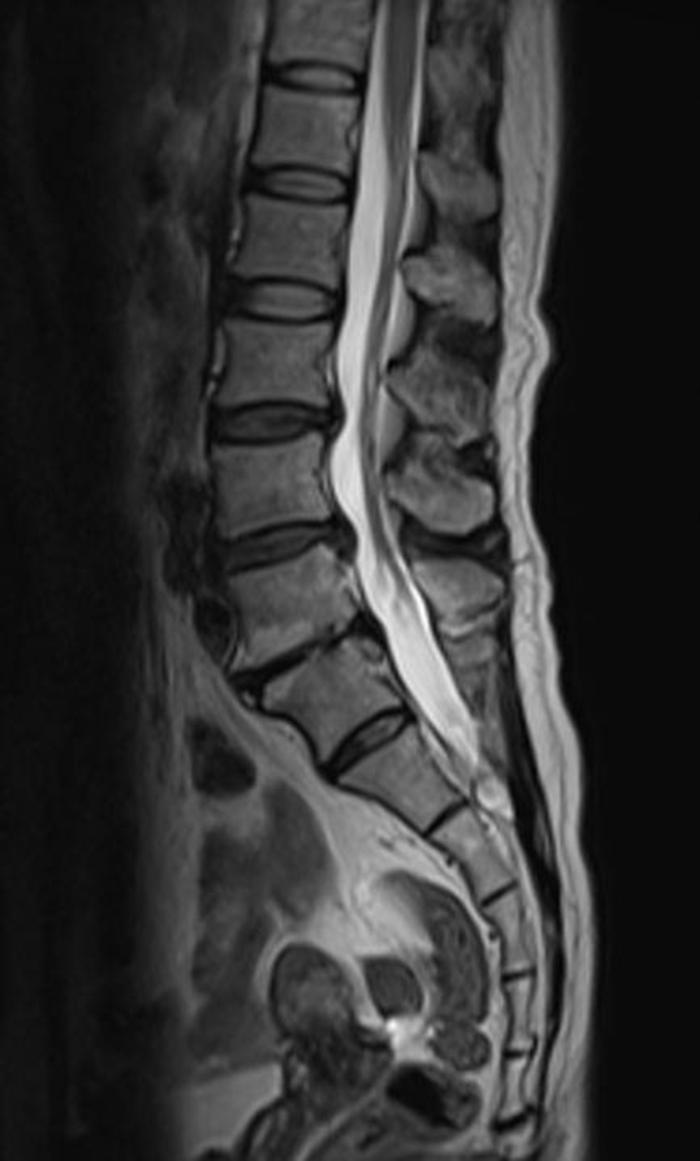

中年女性,骶管小囊肿,当地医院2年前手术,术后症状加重,骶尾臀部剧烈疼痛,VAS 7分,不能站、立、行超过15分钟,术后至今每天服用止痛药。从影像来看,骶管囊肿并不大,为何术后疼痛这么明显呢?应该怎么处理呢

术中:1. 骶管囊肿虽然很小,但漏口很大;予以严密的封堵;2. 由于初次手术未修补骶骨骨窗,所以患者不能久站,本次手术用钛板修复骨窗,重建一个骨性的压力屏障。

术后疼痛明显减轻,没有再吃过止痛药,每天行走6000步以上。还在继续恢复改善。